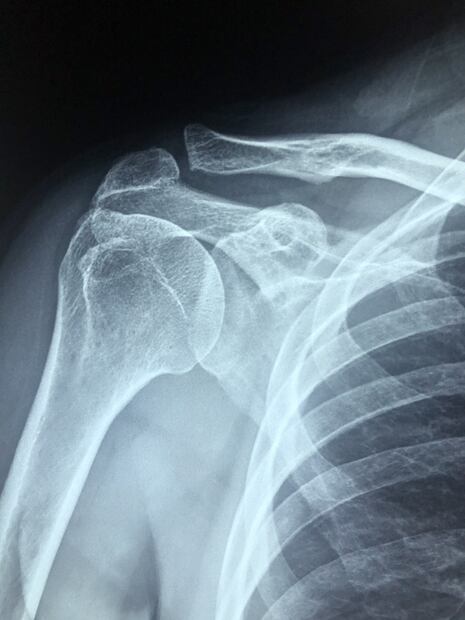

Los rayos X son pequeñas ondas electromagnéticas que permiten observar el interior del cuerpo humano. Pare ello, se valen del uso de mínimos disparos de radiación al cuerpo y en este los tejidos las van absorbiendo.

Por ejemplo, el calcio de los huesos absorbe la mayoría de estos rayos X y en la imagen final se verán de color blanco. Los tejidos blandos absorben menos radiación, por lo que se verán de color gris y la menor cantidad es absorbida por el aire, que resultarán en un color negro.

Esta técnica, es una de las más utilizadas y permite, entre otras cosas, detectar huesos rotos, neumonías y hasta cáncer de mama. En el ámbito de la salud, los rayos X es algo recurrente y un apoyo fiel con el que los profesionales cuentan para llegar a un diagnóstico preciso y saber cómo proceder en cuanto a tratamientos.